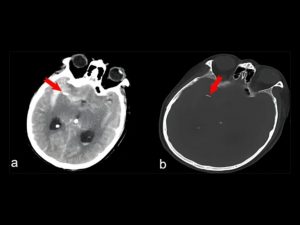

È il caso di un uomo di 74 anni che si è rivolto ai medici per uno stato di coscienza alterata: una Tac alla testa ha però rivelato la presenza di corpo estraneo appuntito che stava causando un’emorragia cerebrale. Era un ago per l’agopuntura lungo circa 1 cm, che era lì da circa 20 anni.